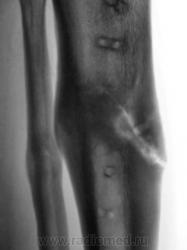

Щелевидный дефект до 1/2 d кости обусловлен, по всей вероятности, необезыствленной остеоидной тканью. Со временем "захряснет". Клиницисты в таких случаях констатируют консолидированный перелом.

СОСТОЯНИЕ КОСТНЫХ ОТЛОМКОВ УДОВЛЕТВОРИТЕЛЬНОЕ. ЛИНИЯ ПЕРЕЛОМА НЕ ОПРЕДЕЛЯЕТСЯ. ИЗБЫТОЧНАЯ КОСТНАЯ МАЗОЛЬ. А ДЛЯ ЧЕГО МСЭК?

Пациент борется "за группу" применяя все тактические дозволенные и не дозволенные действия. На мой взгляд , некоторая избыточная костная мозоль есть. Длинник кости сохранен.

Консолидированный  перелом костей голени на границе верхней и средней 1\3 диафизов. Состояние костных отломков удовлетворительное. Линия перелома, практически, не визуализируется. В б\б кости линия простветления до 1\2 поперечника, обусловленная дефектом костной ткан. Определяется избыточная костная мозоль. В верхней и средней 1\3 дефекты костной ткани как следствие перенесенной операции МОС. А на основании чего этот упорный пациент надеется получить группу?!  Все сопоставлено, срослось...  ???

Линия перелома хорошо видна на боковом снимке

Видна линия «просветения», в которой содержание солей кальция понижено. Но она не является линией перелома и пересекает не весь поперечник утолщенного диафиза. Главное: опорная функция восстановлена?